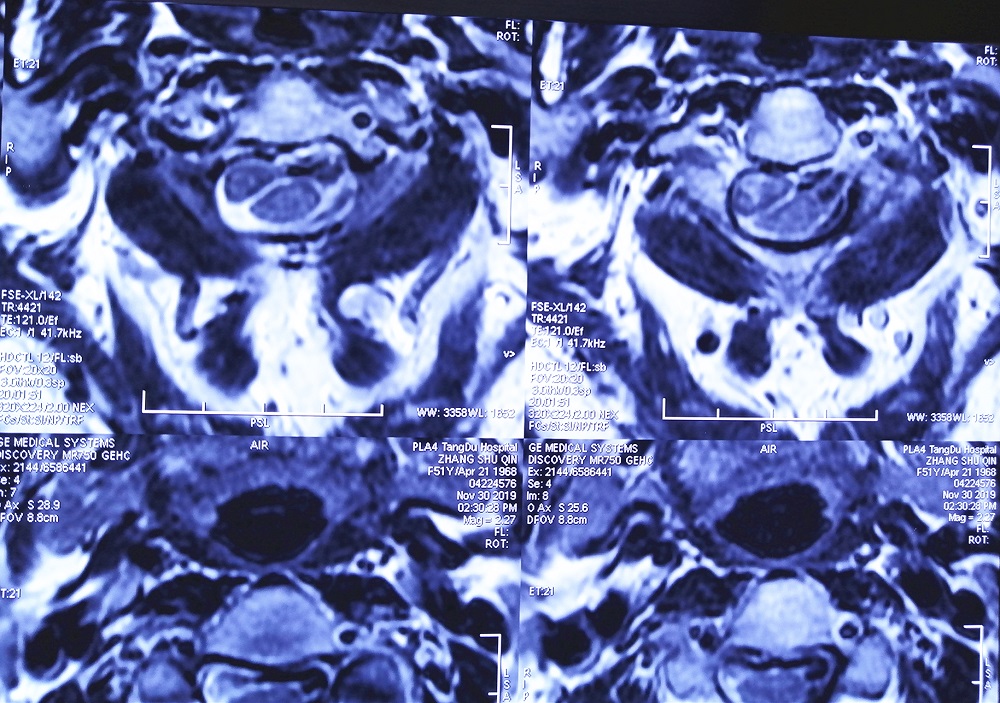

结果颈椎核磁共振检查发现,马女士颈2椎管内肿瘤(术后病理检查为脊膜瘤),颈5-6、6-7出现颈椎间盘突出,并且还有颈椎骨质增生。

​术前影像学检查